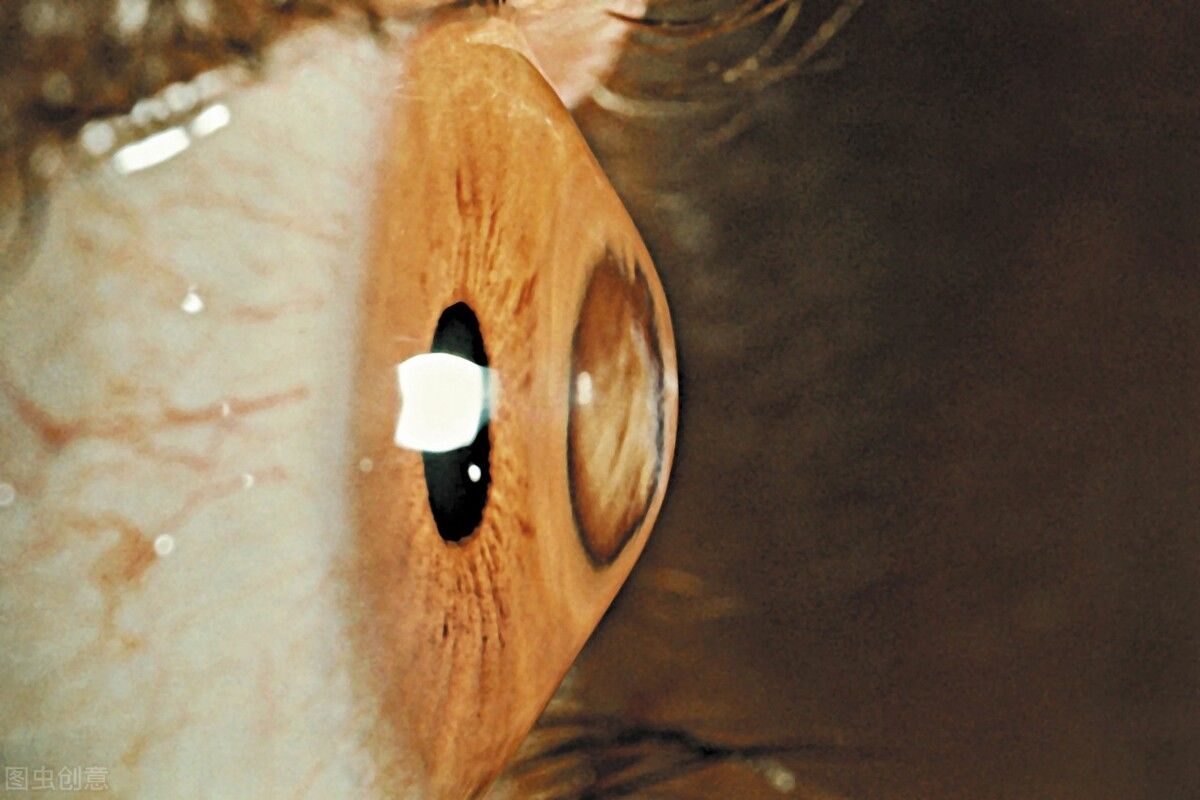

所谓的圆锥角膜是一种先天性的眼病,简单来说,就是角膜中间向前凸出,看上去就像一个圆锥体。因为角膜不断往前凸,不断变薄,导致角膜形状、曲度等都会发生改变,所以会出现近视和散光。

文章插图

“小郑来得有点迟,已经处于圆锥角膜完成期,可以看到他眼睛椎体形态已经很明显了,现在他的情况不适合做角膜交联手术,只能安排角膜移植。”董诺主任向我们说到。